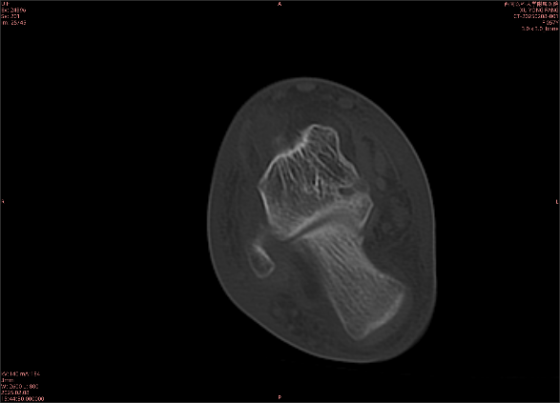

為什么DR和CT基本無(wú)法診斷?(專業(yè)科普)

由于無(wú)骨皮質(zhì)中斷,尚不足以引起X線衰減系數(shù)的明顯改變,X線平片無(wú)異常征象;CT在顯示骨皮質(zhì)及軟組織異常方面明顯優(yōu)于傳統(tǒng)X線,特別是三維重建能夠有效的評(píng)價(jià)復(fù)雜骨折,骨外傷CT檢查應(yīng)用廣泛,但CT對(duì)隱性骨折的顯示亦極為有限。

舉例圖像

圖2

專業(yè)解釋看不懂沒(méi)關(guān)系,大家看圖1和圖2就可以了,這是同一個(gè)患者跟骨的磁共振和CT圖像,圖1的紅色箭頭指示的黑線就是磁共振圖像顯示的骨折線,一目了然。而對(duì)比圖2的CT圖像上并未顯示異常。